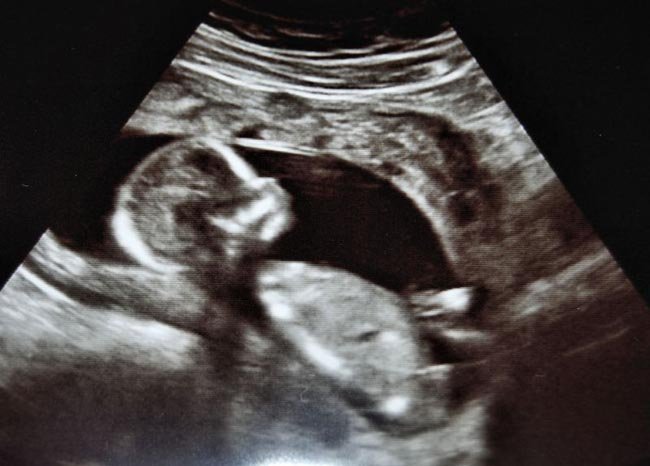

La tercer ecografía se suele realizar entre la semana 33 y 35 de gestación. Es ya la útima ecografía antes del nacimiento del bebé, por lo que sirve principalmente para obtener información acerca de cómo se desarrollará el parto.

Además de valorar el estado del feto, su crecimiento, los latidos cardíacos y los movimientos, sirve también para conocer su posición dentro del útero:si ya está boca abajo, si está encajado en la pelvis, si no lo está, si está de nalgas, etc.

Como el bebé ha crecido bastante a estas alturas, en la ecografía se pueden ver sólo partes de su cuerpo.